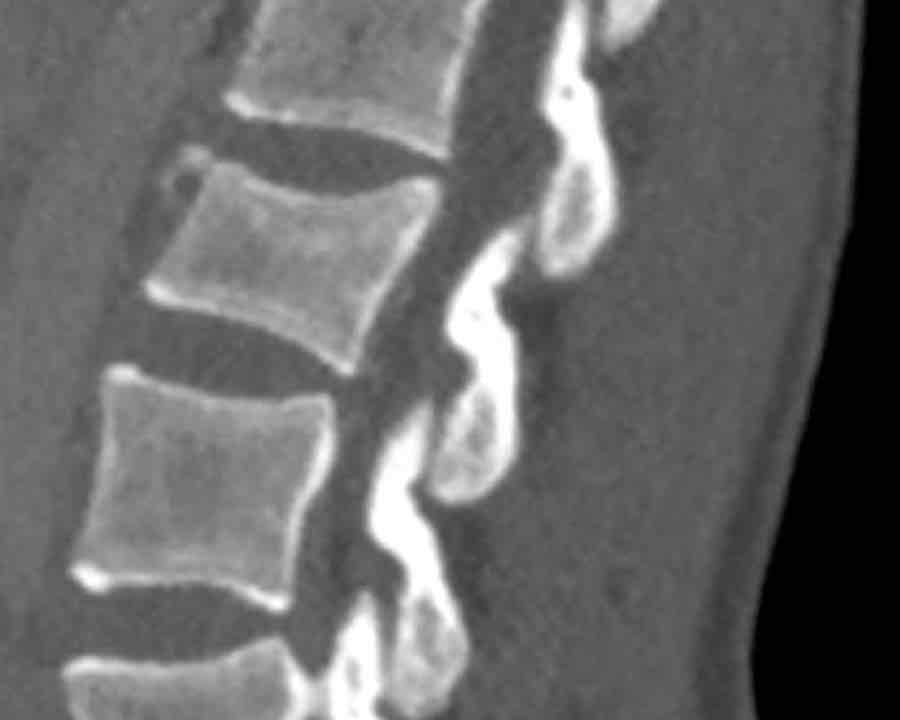

A3 Incomplete Burst fractures

Fracture with any involvement of the posterior wall; only a single endplate fractured.

A vertical fracture of the lamina is usually present and does not constitute a tension band failure.

What is the AO-type of the vertebral body fracture based on only these two inages?

Findings:

- Fractures of the vertebral body with involvement of upper endplates (1 points) and posterior wall (2 points)

- Bulging of the posterior wall without any other signs of dislocation is the result of the burst fracture.

Therefore no C injury.

Conclusion

Injury type A3